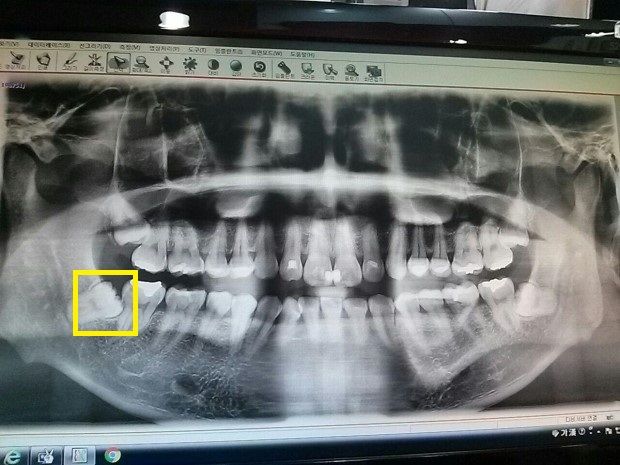

구강외과에서 들은 설명대로 적자면 아래쪽 사랑니와 어금니 사이의 인접면에 검은 선이 얇게 있는데 저기가 빈 공간이라고 하셨습니다.

위의 사진은 2019년이지만 어제 본 2023년 사진과 비교해봐도 노란색 부분의 검은 선이 커진 거 같진 않습니다. (사진은 클릭하면 커집니다.)

선생님에게 노란색 부분의 사랑니와 어금니 사이의 검은 선에 대해 제가 썩은 거냐고 질문하니 그렇다고 답변하셨고요.

매복 사랑니가 앞의 어금니의 뿌리 부위를 침범한 것으로 보입니다

이 경우 앞에 어금니의 뿌리가 흡수 되어 치아가 흔들리고 통증이 생기는 문제가 발생할 수 있으므로 뽑아주시는 것이 좋습니다

매복 사랑니의 경우 앞의 치아는 잇몸 속에 있어 치료가 불가능 하므로 문제 부위가 더 커지거나 통증이 발생하는지 보고 문제가 있다면 치료해줄 수 있습니다